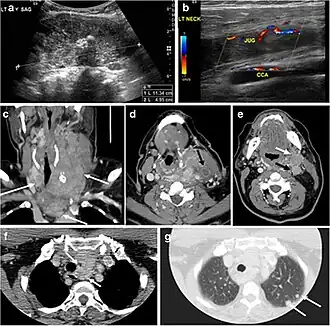

Fig. 4. A 45-year-old male patient presented with anterior mediastinal metastatic PTC lesions and occult primary on imaging. Histopathology examination of the resected thyroid gland revealed micro-foci of PTC; the largest, in the isthmus, measured 4 mm. a transverse greyscale ultrasound of the thyroid demonstrates homogeneous gland with normal echogenicity and size. No focal lesion or micro-calcifications. b Non-enhanced CT scan obtained as part of PET/CT examination shows a heterogeneous, large, relatively dense anterior mediastinal mass (white arrow) with peripheral calcification (arrowheads). Thyroid gland has normal CT appearance with no abnormal FDG uptake (not shown).[1] -

Finally, the possibility of metastatic disease should be excluded. PTCs and medullary thyroid carcinomas tend to metastasize to regional lymph nodes. According to the AJCC/UICC TNM staging system, the nodal stage is classified by site: N1a indicates level VI nodal involvement, including paratracheal nodes; N1b indicates unilateral or bilateral lateral cervical nodal disease or superior mediastinal nodal disease (Figs. 4, 55 and and6)6).[1]

Surgery is the primary mode of treatment for DTCs. Post total thyroidectomy radioactive iodine (RAI) ablation is an option, especially in patients with distant metastasis, tumours larger than 4 cm, or extra-thyroidal disease extension. Ultrasound examination is usually adequate in evaluating primary tumours and cervical lymph nodes. Preoperative cross-sectional imaging with CT or MRI is indicated if there is a concern for local invasion that may alter the patient's staging as well as surgical approach (Figs. 4, 55 and 6)6) . Some thyroid primaries may be small, diffuse, or multifocal and therefore may be occult on imaging (Fig. 4) .[1]